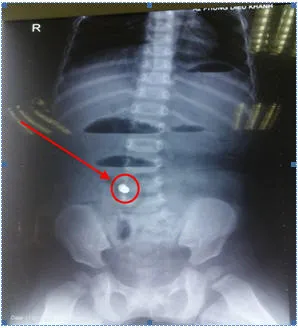

Dị vật được lấy ra ngoài - Ảnh do BS cung cấp

Qua thăm khám và chụp X-quang, siêu âm bụng, các BS phát hiện có hình ảnh của dị vật trong bụng của trẻ, chẩn đoán tắc ruột do nuốt phải dị vật. Trẻ được mổ nội soi cấp cứu. Kết quả tìm thấy có đoạn ruột giãn và đoạn ruột xẹp (ranh giới chỗ tắc ruột), tại ranh giới này thấy có dị vật hình trụ đường kính 0.5cm, dài 1 cm gây viêm hoại tử thành ruột lộ ra ngoài, dính với mạc treo tạo đọan gập góc gây tắc ruột. Các BS đã tiến hành mở rộng vết mổ tại rốn (khoảng 2cm), đưa đoạn ruột tổn thương ra ngoài, cắt đoạn ruột bị tổn thương có chứa dị vật khoảng 5 cm (có 4 dị vật dính với nhau), nối lại ruột. Theo các BS, dị vật này chính là bốn hạt kim loại có từ tính giống như nam châm, có khả năng hút nhau.